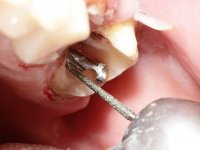

Teeth 17 and 16 were prepared for the fabrication of a 2-element Zr bridge. The impression was performed with a double mixing technique and a monolithic bridge in Zr was made in the laboratory. 4 years later, an abscess appeared in the apical area of tooth 26. It was decided to remove the bridge, remove the intra-radicular posts and retract the endodontic treatments of teeth 17 and 16. The removal of the bridge was carried out by making two cervical cavities. in the palatal area of the bridge and with a microluxator, disinsertion movements were performed. The intra-radicular posts were removed using fine drills and an ultrasound tip. The bridge was provisionally cemented and the patient was referred to a fellow endodontist for endodontic retreatment. After the retreatment, the intraradicular posts were placed again and the bridge was definitively cemented. One year later, a new abscess appears, possibly related to a root fracture. The bridge was sectioned between tooth 27 and 26 and tooth 26 was extracted and the crown of 27 was provisionally cemented. 3 months later, teeth 27 and 25 were prepared and a temporary bridge was made in dual polymerization resin. Then, an impression was made using the double mixing technique and a 3-element bridge in Zr was made in the laboratory. It was permanently cemented in the mouth with resin-reinforced glass ionomer cement.